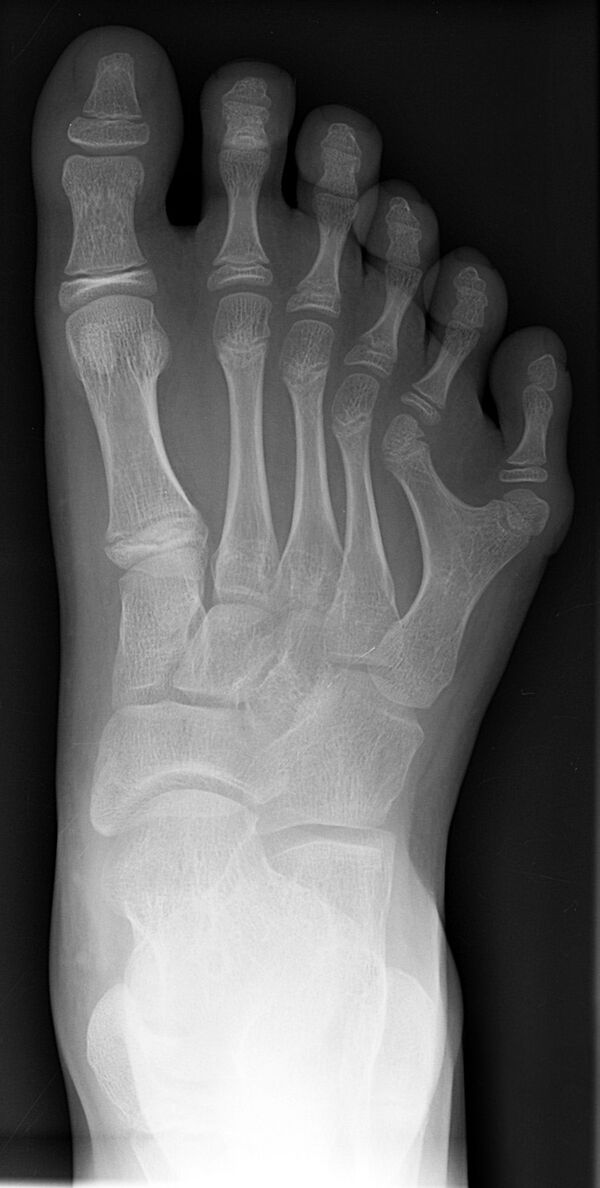

Полидактили́я (др.-греч. πολύς — много + δάκτυλος — палец, синоним — многопалость), также известная как гипердактилия — порок развития, характеризующейся бо́льшим, чем в норме, количеством пальцев на руках или ногах у человека, собак, котов и лошадей. Противоположным отклонением является олигодактилия.

У людей и животных она может проявляться как на одной, так и на обеих руках. Обычно дополнительный палец представляет собой небольшой кусочек мягкой ткани, которую можно удалить. Иногда это просто кость без суставов; очень редко лишний палец бывает полноценным. Дополнительный палец чаще всего образуется со стороны мизинца, реже на стороне большого пальца и очень редко между средними пальцами. Обычно лишний палец является аномальным разветвлением обычного пальца, редко возникает на запястье, как обычный палец.